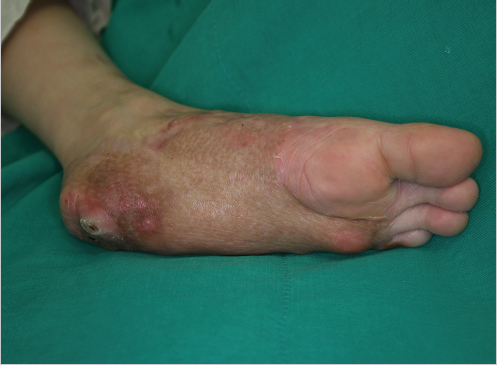

Muscle flaps are frequently needed to cover large defects of the extremity and foot. Free muscle flaps with skin grafts have been traditionally popular, considered to be easier in tailoring into the soft-tissue defects, providing good cushioning and solid anchorage to the deep structure and thus can best replace the complex subcutaneous architectural structure of the plantar surface.3,5,6 But questions have been raised with regard to their durability against long-standing pressure.7,8 In muscle flaps that were used to reconstruct the foot without reinnervation, gait and stance analysis with nonsensory innervated muscle flaps revealed the ability to bear weight, but with decreased pressure and duration.1,2,3 Other reports speculate that functional reconstruction outcome may be more related to underlying bony deformities.9 Nevertheless, muscle flaps with skin graft to reconstruct the foot may be bulky and require frequent secondary debulking proceudres.3 Furthermore, frequent ulceration has been reported with muscle flaps with skin grafts that may need high maintenance (▶ Fig. 19.1).3 This is most likely due to the lack of normal skin anatomy and sensory recovery. Although there have been multiple reports that muscle flaps regain deep pressure sensation even without cutaneous innervation, they will never regain complete sensory recovery.1,2,3,10 Muscle flaps with intact motor nerves or with reanastomosis of the motor nerve to suitable motor or sensory nerves at the recipient site may have higher chance to retain protective sensibility.1,2,3 Nevertheless, with good maintenance involving visual inspection, proper footwear, and daily management, muscle flaps do provide a good solution especially for extensive defects of the foot.